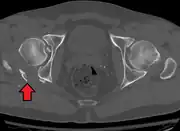

Axial CT image (viewed on bone windows) of a complex comminuted left acetabular fracture involving both anterior and posterior columns.

In all cases, CT scan can assist in identifying impacted bone pieces, which may be found within the joint, and MRI may be done to identify the extent of potential injury to the sciatic nerve.